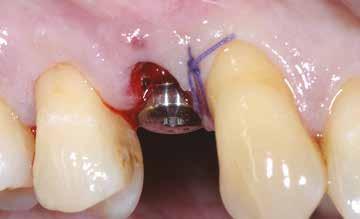

3. ábra: A sablon illeszkedése az ablakokon keresztül ellenőriz hető, az implantáció végig a sablonon keresztül történik.